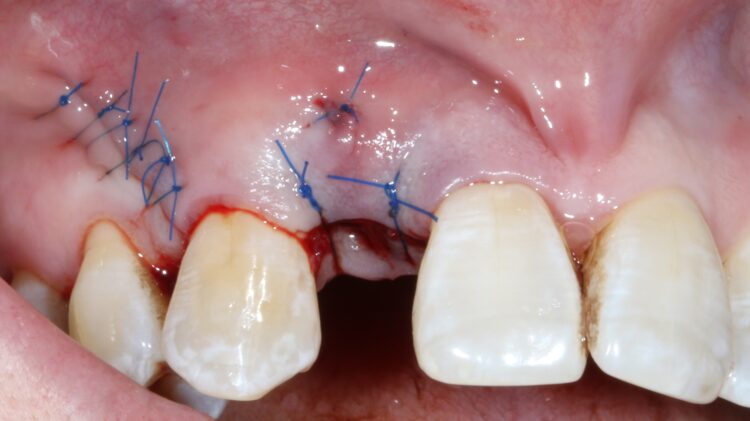

The muco-periosteal flap was sutured back with 6.0 Prolene and no attempt was made to coronally advance the flap for complete closure. The rationale was to maintain the open socket wound and thereby preserve the original mucogingival relationship with no alteration. The socket entrance was sealed with the short acting membrane, while the original tooth (after root removal) was utilised as a temporary pontic and bonded to the adjacent teeth with flowable composite.

A free gingival graft was taken from the palate below the upper right molar teeth and the epithelium was removed on the surgical table. The connective tissue strip of graft was then placed on top of the healing cap (and suspended over the healing cap) and secured to the palatal flap with 6.0 PGA Resorba Sutures. Finally, the buccal flap was closed with complete primary intention wound healing using 6.0 Prolene.